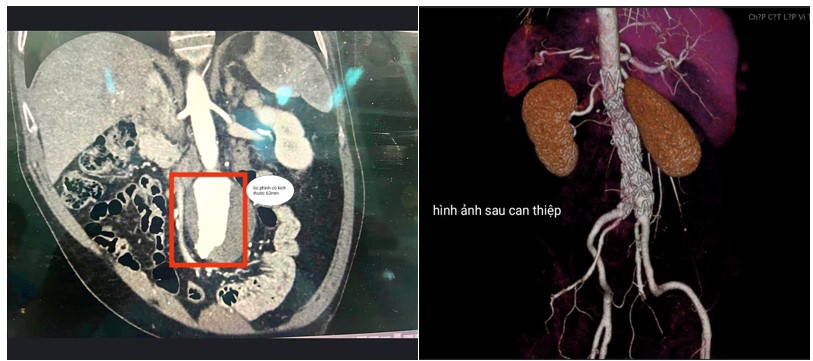

Sau khi được thăm khám, làm các xét nghiệm cần thiết, các bác sĩ phát hiện trên phim chụp cắt lớp 128 dẫy, bệnh nhân có khối phình động mạch chủ bụng với kích thước 63x 83mm, có xơ vữa dày 17mm, kèm phình động mạch chậu chung phải 22mm và động mạch chậu trái 27mm. Nhận định đây là khối phình lớn có nguy cơ vỡ rất cao và nguy hiểm đến tính mạng nếu không được can thiệp kịp thời, các bác sĩ đã quyết định tiến hành đặt Stent Graft cho bệnh nhân.

Hình ảnh trên CLVT trước và sau khi can thiệp

Sau 1 tuần theo dõi và điều trị theo phác đồ, kết quả chụp cắt lớp vi tính MSCT 128 lát cắt cho thấy Stent Graft đúng vị trí, không có rò cạnh Stent, sức khoẻ bệnh nhân hồi phục tốt và đã được ra viện ngày 12/6/2023.